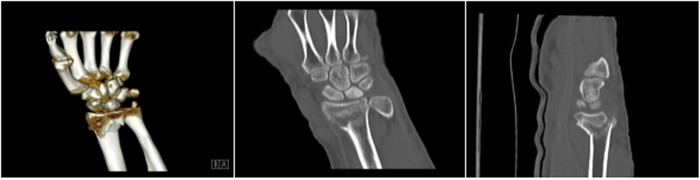

明峰CT搭載了領(lǐng)先的硬件技術(shù)平臺(tái)及系統(tǒng),強(qiáng)大的掃描能力可滿足臨床的各種要求,呈現(xiàn)更極致的細(xì)節(jié),為各臨床科室提供高品質(zhì)的圖像。薄層掃描,消除部分容積效應(yīng),提高各向同性。配合高分辨率算法,有助于細(xì)微結(jié)構(gòu)和形態(tài)學(xué)顯示。